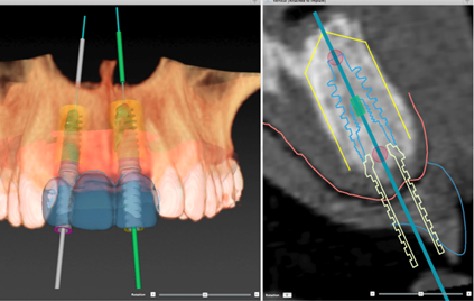

瑞典“诺贝尔”种植牙系统是基于计算机引导下的自动设计和激光定位,这种方式由原来的手工操作专为自动化处理,整个过程由电脑控制并完全按照电脑模板进行,如果医生在手术过程对植入的位置和深度掌握稍有偏差,电脑会自动停止手术操作,从而确保植入部位的精准和安全。因为是根据电脑模板的引导处理,所以过程更加精密,手术时间也大大缩短,常规种植每颗牙平均只需5-10分钟左右,一小时种出一口牙也能成为现实。